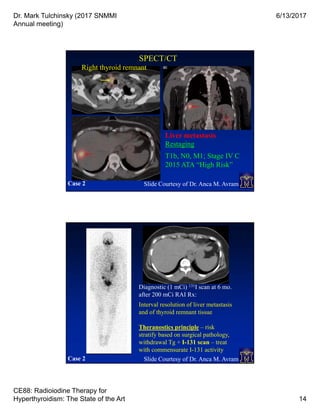

Restaging

T1b, N0, M1; Stage IV C

2015 ATA “High Risk”

SPECT/CT

Liver metastasis

Case 2 Slide Courtesy of Dr. Anca M. Avram

Right thyroid remnant

Diagnostic (1 mCi) 131I scan at 6 mo.

after 200 mCi RAI Rx:

Interval resolution of liver metastasis

and of thyroid remnant tissue

Theranostics principle – risk

stratify based on surgical pathology,

withdrawal Tg + I-131 scan – treat

with commensurate I-131 activity